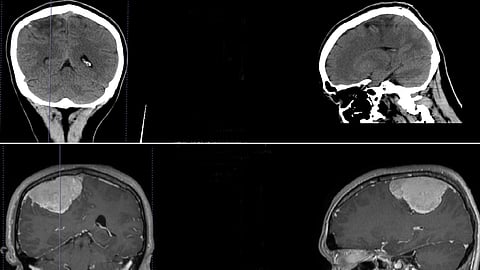

وبعد إجراء الفحوصات الطبية المتقدمة، تبيّن وجود ورم دموي ضخم ضاغط على مراكز الحركة والإحساس بالمخ، مما شكل خطورة بالغة على حياته.

ونظرًا لخطورة هذه الحالة وتعقيدها، تم على الفور تحضير المريض لإجراء عملية جراحية دقيقة تُعد من أصعب وأدق جراحات المخ والأعصاب نظرًا لملاصقة الورم للمراكز الحيوية بالمخ وصعوبة استئصاله.

وبفضل الله ثم بفضل خبرة الكادر الطبي في القسم، وباستخدام أحدث التقنيات العالمية في هذا المجال مثل التدخل المحدود والميكروسكوب الجراحي، أُجريت العملية عبر جرح صغير لم يتجاوز 5 سم فقط.